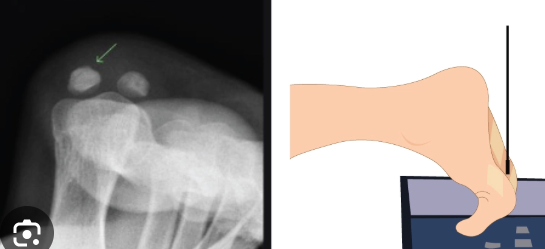

How do you position for prone and supine sesamoid bones?

A

Prone or supine. Free of superimposition, minimum of 3 metatarsals seen

How are sesamoid bones in toes imaged?

Pressing toes dorsiflexed or pulling toes dorsiflexed

123

Sesamoid toe criteria

Free of superimposition Min 3 metatarsals seen